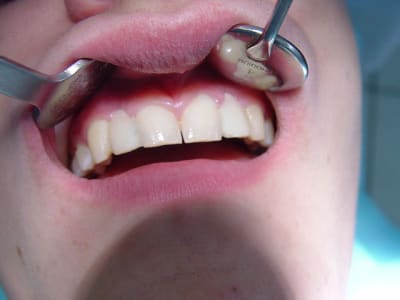

résultat premier bridges collés Emax

à voir dans le temps...

gestion du temps provisoire pas évident

surtout sur un étudiant présent que le WE..

et encore désolé pour l'iconographie (pas ma préoccupation majeure car un peu pris ds le rythme .. )

Dsc00086 ndjykx - Eugenol

Pc220001 yewrw6 - Eugenol

Pc220002 h71mzd - Eugenol

Pc220008 xfltj8 - Eugenol

ça a vraiment le mérite d'avoir ete tenté , bravo ! surtout sur un etudiant , patient à vie risquée (sandwich, barre cereales etc ...) donnera une bonne idee du futur .

et puis le résultat est top compte tenu de la situation spaciale des collatérales ...beaux rendu de teinte et aussi du collage des canines ...

Pourquoi ne pas avoir "travaillé" plus les embrasures, la papille va pas etre contente.

fraise tungstène spéciale c'est encore faisable, sans compromettre la solidité.

belle teinte.